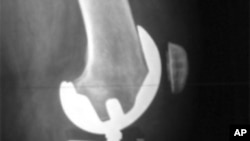

X光照射显示人工的膝关节

数百万的美国人患有骨关节炎,又称退化性关节疾病。病情严重的需要做人工关节替换手术。人工关节可能是用合金、塑料和陶瓷制成的。不过,新的研究显示,利用病人自己的干细胞,有可能修复受损的关节。

骨关节炎通常使用止痛剂和消炎药治疗。但是病情严重时,可以考虑用人工关节替换受损的关节。不过,这种选择并不适于人数越来越多的年轻患者。